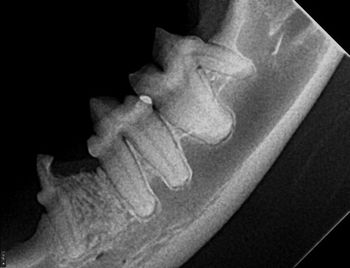

Tooth resorption is present in almost all our patients, but how do you classify it, and when do you treat it? Veterinary dentist Dr. Mary Volker has answers.